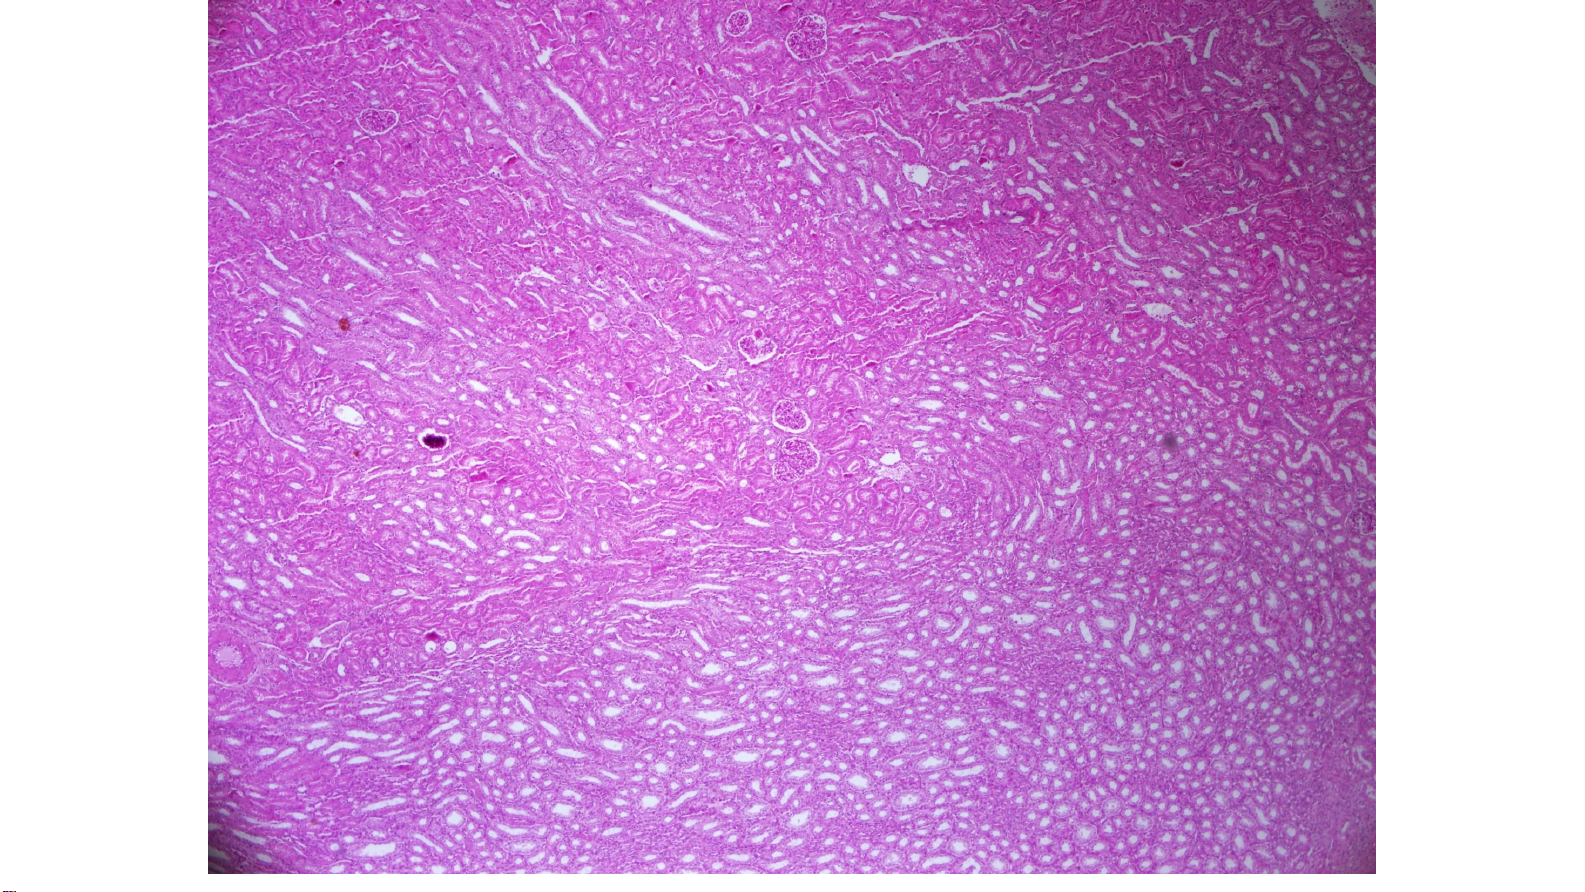

Histology_ A Text and Atlas_ With Correlated Cell an Molecular Biology THẬN •Vùng vỏ:

o Tiểu cầu thận, ống thận

o Tia tủy ( tia Ferrein): ống góp và đoạn thẳng của quai Henle

o Trụ Bertin( trụ thận): nằm giữa các tháp thận 7 BỘ MÔN MÔ- PHÔI- PNT 9 BỘ MÔN MÔ- PHÔI- PNT 10 THẬN •Vùng tủy: